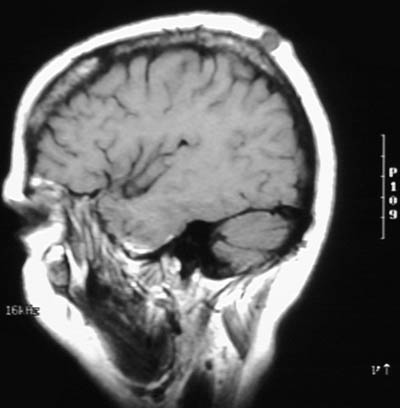

| The sagittal T1 weighted MRI scans of the head above and below reveal cysts in the scalp. The subcutaneous fat of the scalp is bright, while the acellular keratinaceous contents of the epidermal inclusion cysts are dark. A portion of epidermis trapped under the skin surface may continue to slowly grow and desquamate, producing the cyst. These cysts are seen most frequently on face, scalp, neck, and trunk. They are about 1 to 5 cm in size. |